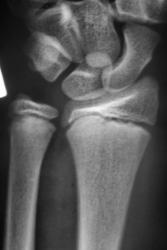

Пациент направлен врачом хирургом в рентгеновский кабинет для рентгенографии лучезапястного сустава. Произведено стандартное исследование. Ваше мнение уважаемые коллеги?

Продольный перелом лучевой кости.

Перелом - эпифезиолиз и продольная трещина в луче, смешение периферического фрагмента к тылу на приблизительно 20 градусов

Перелом луча без смещения. А вообще - головка локтевой кости смущает... или полупроекция?... Доснять бы в/3 предплечья - возможно повреждение Галеацци

В руководстве  Interpreting Trauma Radiographs Jonatan McConell et al. Blackwell Publishing 2005 p. 130 говорится о нормальном угле в боковой проекции в 10 -15 градусов. В представленном наблюдении угол составляет около 95-98 градусов (транспортира под рукой не оказалось), что говорит об угловом смещении периферического фрагмента к тылу на угол от  16 до 23 градусов.